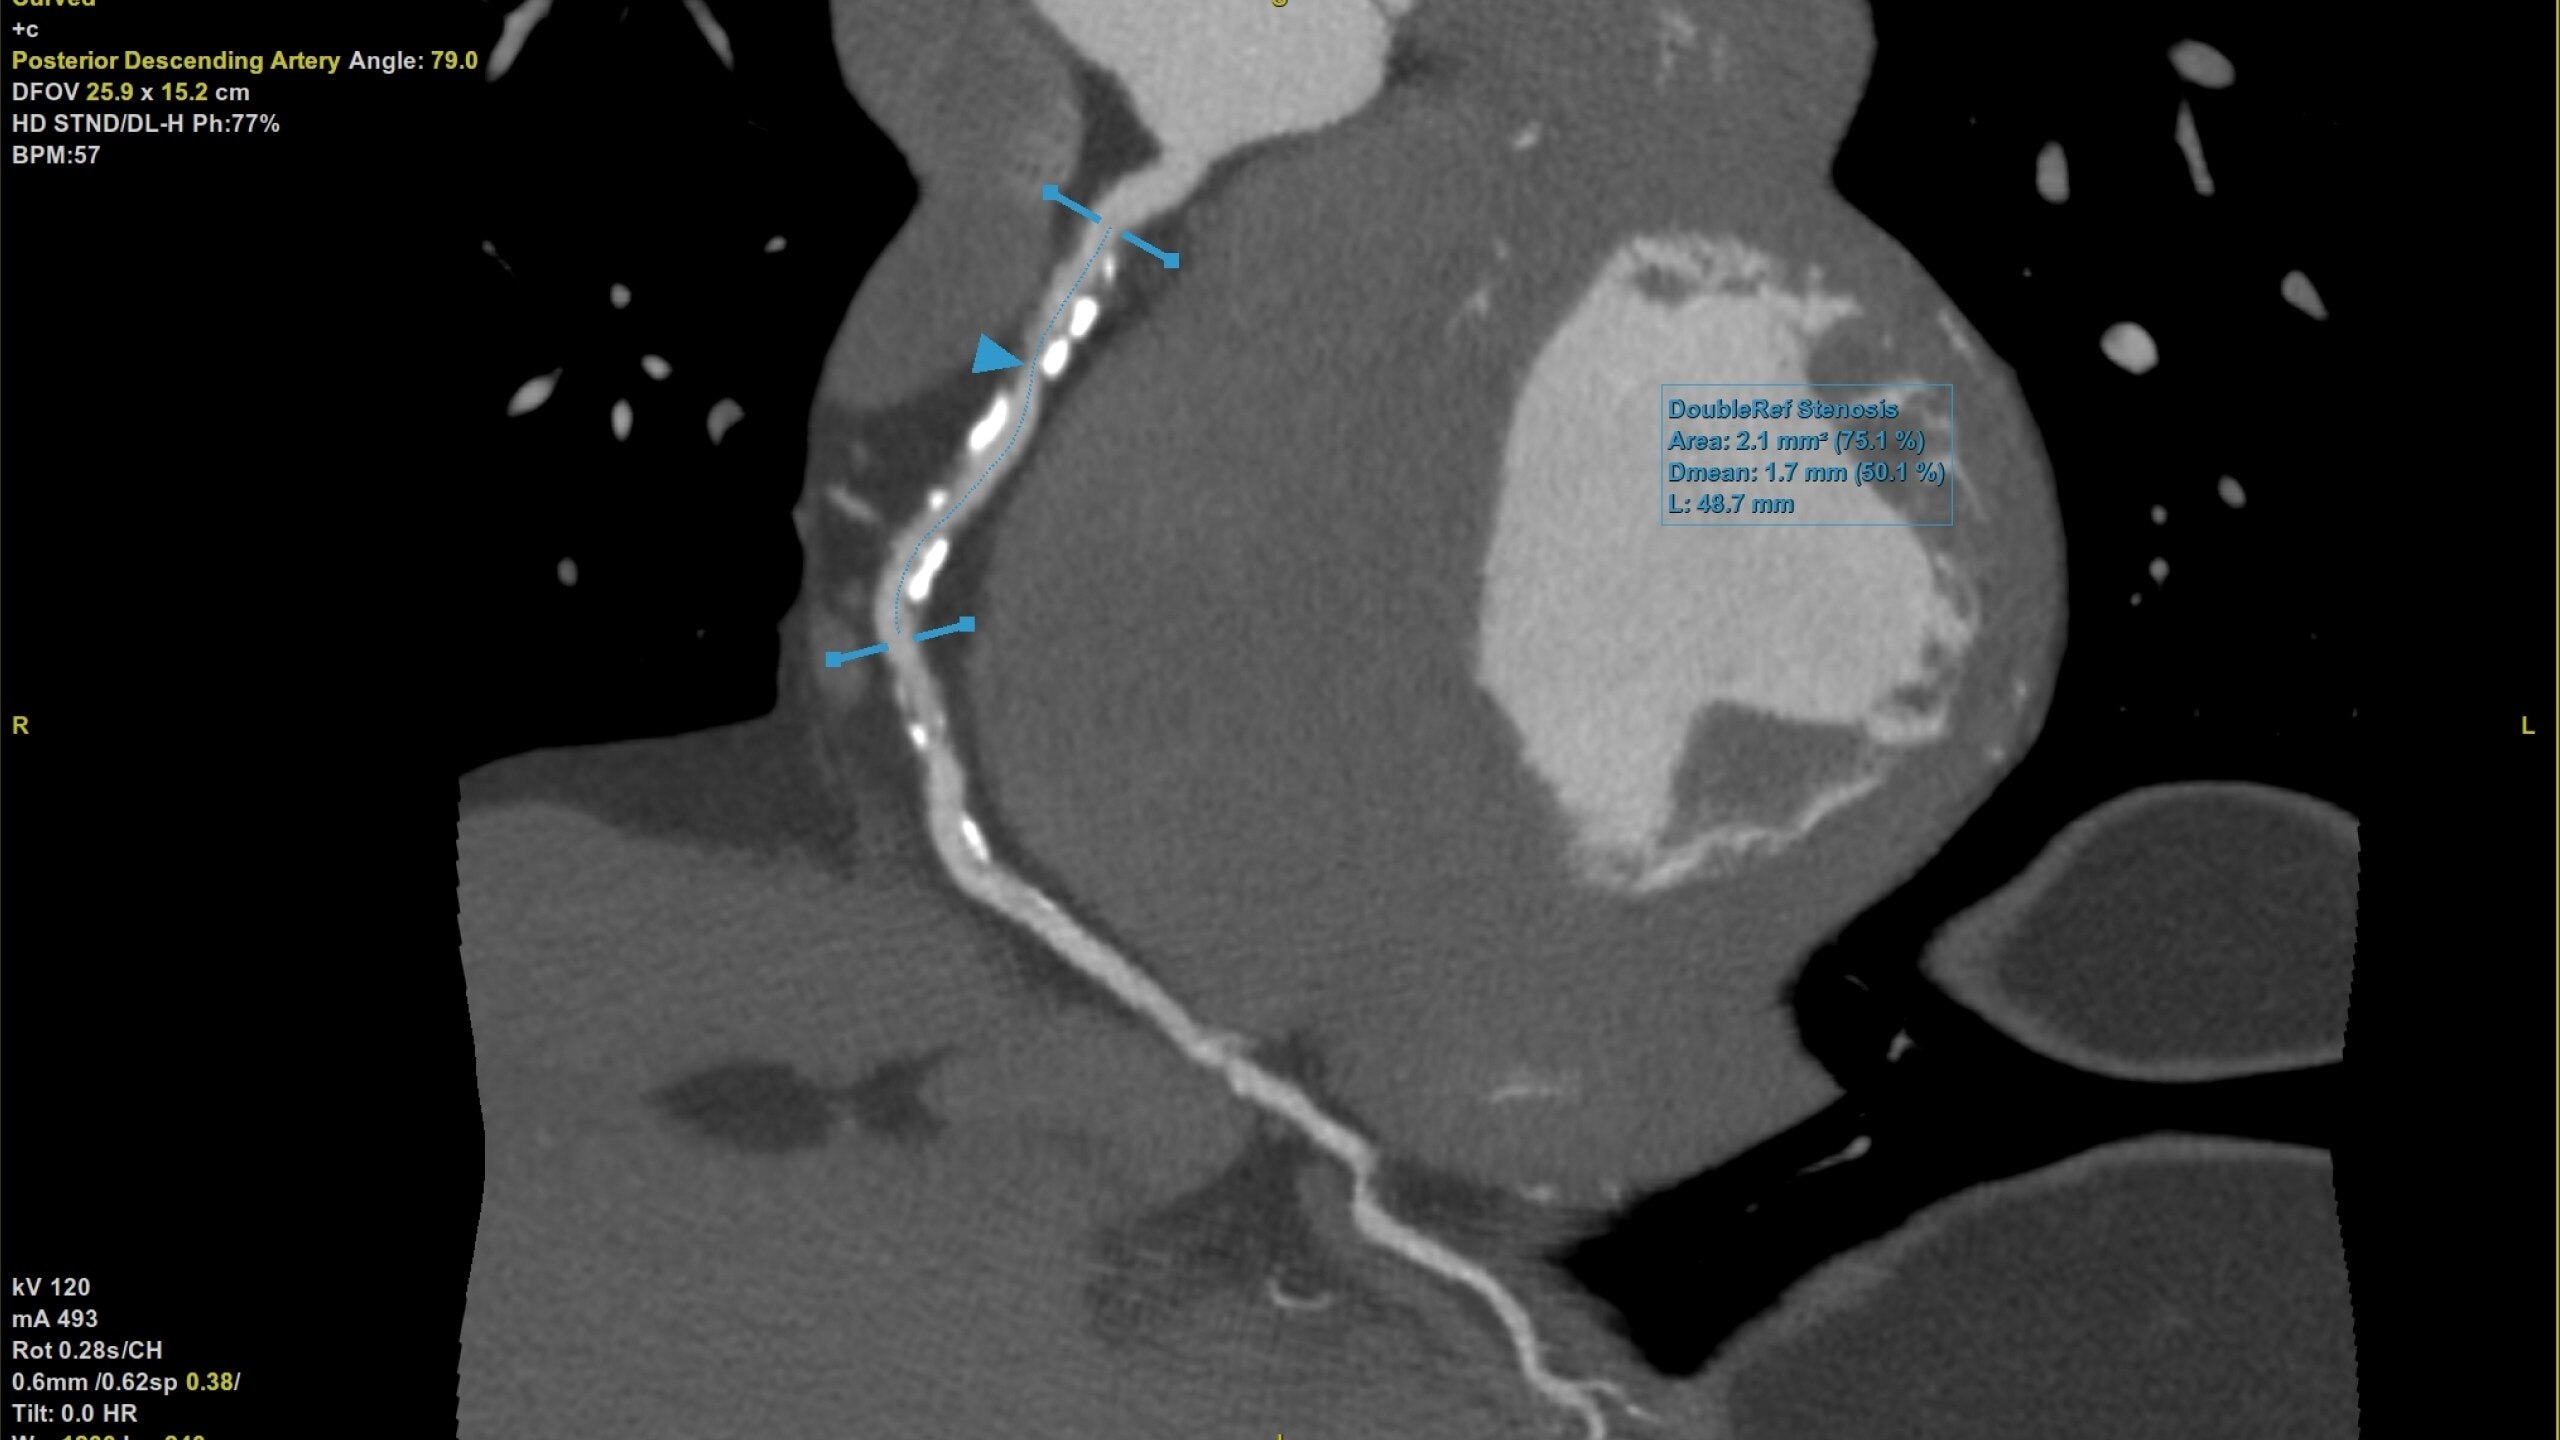

• Plaque ID provides volume measurements for four

distinct Hounsfield ranges to aid with identification and

visualization of coronary plaque